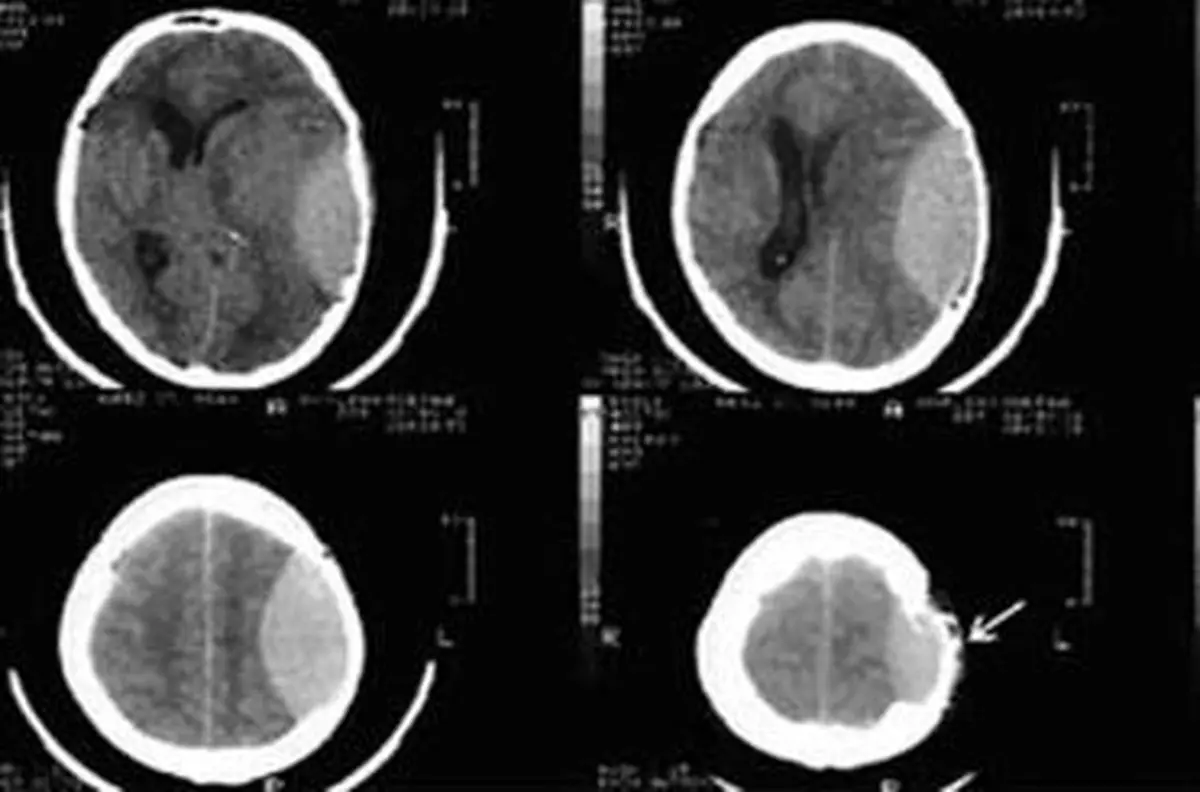

محققان موفق به طراحی نرم افزار دستگاه سی تی اسکن ۴ بعدی مبتنی بر مفهوم واقعیت افزوده شدند.

سعید بیات مدیر عامل یک شرکت دانش بنیان در خصوص طرح خود با عنوان «نرم افزار دستگاه سی تی اسکن ۴ بعدی مبتنی بر مفهوم واقعیت افزوده» گفت: این نرم افزار در ابتدا عنوان پایان نامه‌ای در مقطع کارشناسی ارشد بود که مورد استقبال قرار گرفت و تبدیل به ایده‌ای برای تولید نرم افزار شد.

وی افزود: در حال حاضر نیز نمونه اصلی این نرم افزار تولید شده و در حال ارتقای آن هستیم. این دستگاه می‌تواند جایگزین دستگاه‌های فعلی با ضریب خطای کمتر باشد.

به گفته بیات، این دستگاه ایرانی حرکات تومور را شبیه سازی می‌کند و در اختیار فیزیک پزشک قرار می‌دهد. این کار کمک می‌کند که سلول‌های سالم اطراف سلول‌های سرطانی، آسیب کمتری ببینند. نمونه خارجی این دستگاه، حدود ۲ میلیون دلار قیمت دارد که قیمت تمام شده دستگاه تولید شده در شرکت ما حدود ۳۰۰ میلیون تومان است، رقمی حدود ۲۴ هزار دلار.